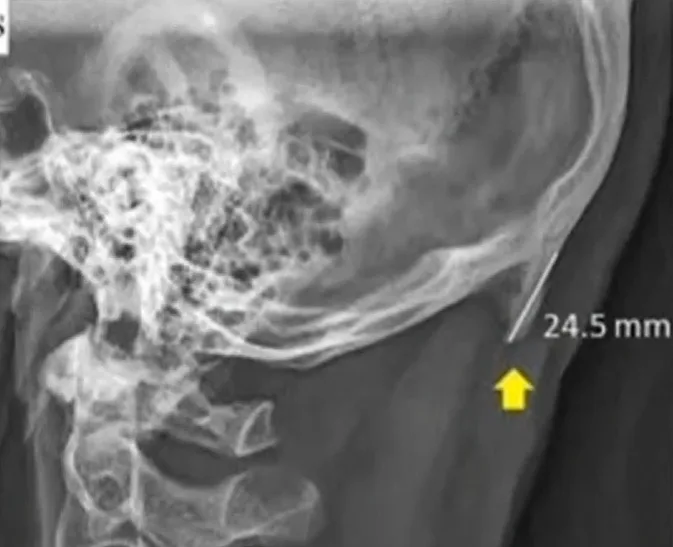

מחקר באוסטרליה טוען שהטיית הראש לצורך בהייה ממושכת במסך הטלפון החכם גורמת לגדילה של מה שנראה כמו קרניים קטנטנות בחלק האחורי של הראש – "עצם הסמארטפון".

שימוש מרובה בטלפונים החכמים משפיע על חיי החברה שלנו, על תפקודנו בעבודה וכעת, לפי המחקר, משפיע ישירות על גופנו. מדענים מאוניברסיטה באוסטרליה בחנו צילומי רנטגן של צעירים וצעירות בני 30-18, וגילו כי כמעט מחצית מהם פיתחו מבני עצם קטנים דמויי קרניים בצד האחורי של ראשם. גודלם בין 31-10 מ"מ, ולטענת החוקרים אפשר להרגיש אותם על ידי מישוש המקום באצבעות.

לטענת החוקרים, גידול הקרניים האלה נובע מהאופן התדיר שבו צעירי העולם מטים את ראשם כדי להתמקד בטלפונים החכמים שלהם, דבר שמפעיל לחץ לא בריא על הצוואר.

"ישנו מחקר שהראה כי היו מעט מאוד אנשים שהתלוננו על כאב שם", הסביר ד"ר דוד שחר, מאוניברסיטת "סאנשיין קואסט" שבאוסטרליה. "קשה למעשה לחשוב על הסבר אחר להופעת העצמות הללו, מפני שצריך לחזור אחורה ולשאול מה קרה בעשר השנים האחרונות שיכול היה להביא לתופעה הזו".